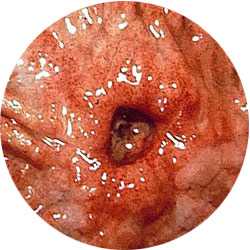

Наилучшим методом является ЭГДС, при которой выполняют множественные биопсии кратера язвы. Рентгенологическое исследование верхнего отдела ЖКТ может помочь в установлении диагноза, однако не является определяющим. Диагноз ставится на основании результатов биопсии. Во время ЭГДС также можно выполнить тест CLO для выявления Я. pylori.

В - Обнаружена доброкачественная язва тела желудка